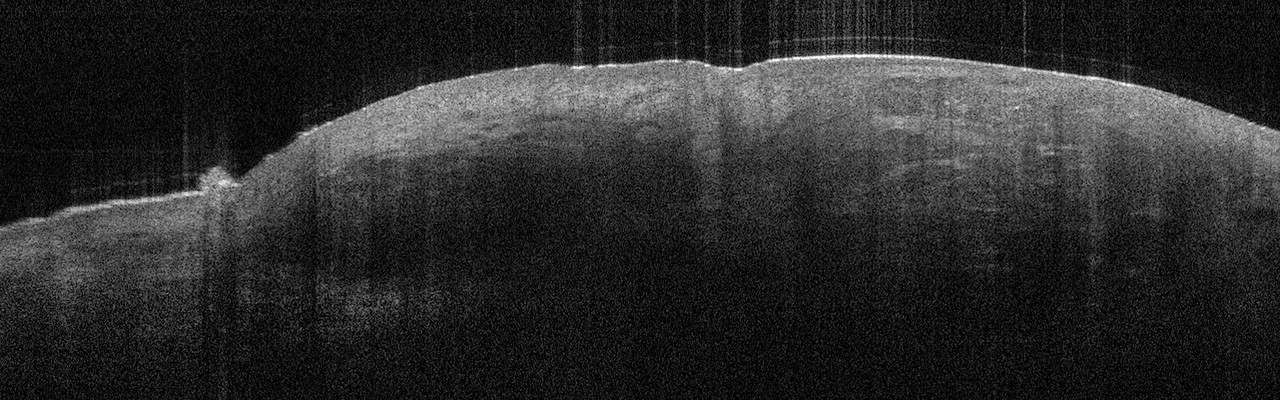

Die Tumorzellverbände des BCC erkennt man in der Aufnahme als signalarme, ovoide Nester mit dunk­lem Randsaum, die von hellem Stroma umgeben sind. Die Epidermis ist abgeflacht, Teleangiektasien kann man als kleine dunkle Löcher sehen. Eine aktinische Keratose sieht anders aus: In diesem Fall sind Hornschicht und Epidermis verdickt, oft sieht man auch weiße Streifen in der Hornschicht, so die Referentin. In Abgrenzung zum Plattenepithelkarzinom erscheint die dermoepidermale Junktion bei der aktinitischen Keratose intakt. Beim Plattenepithelkarzinom werden zudem helle Bereiche deutlich, bei denen es sich um Hornzysten handelt.

Das infiltrative (fibroisierende) BCC ist gekennzeichnet durch schmale dunkle Tumorzellverbände in der Dermis mit nur flachen, helleren Stromabereichen dazwischen – ein Muster, das an einen Fischschwarm erinnert. Das infiltrative (fibroisierende) BCC ist gekennzeichnet durch schmale dunkle Tumorzellverbände in der Dermis mit nur flachen, helleren Stromabereichen dazwischen – ein Muster, das an einen Fischschwarm erinnert. © Prof. Dr. Julia Welzel